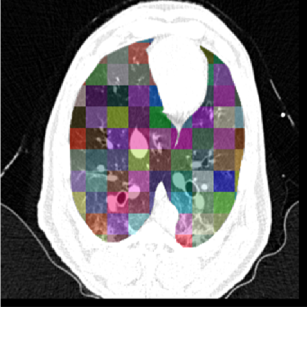

Figure 8(a) shows a comparison between the registration-derived indices of ventilation and the Xe-CT estimated sV in cube-shaped regions of interest for animal D. The corresponding Xe-CT regions in the are divided into about 100 cubes. Figure 8(b) is the Xe-CT estimate of sV. Figure 8(c), (d), (e) are the corresponding registration ventilation measures SAJ, SACJ and SAI. The regions with edema are excluded from the comparison. Figure 8(b) to (d) all show noticeable similar gradient in the ventral-dorsal direction. Notice that the color scales are different in each map and are set based on the range of values from the appropriate plot in Fig. 9.

Figure 9 shows scatter plots comparing the registration ventilation measures and the Xe-CT ventilation sV in all four animals. The SACJ column shows the strongest correlation with the sV (average ). The SAJ, which is directly related to Jacobian as , also shows good correlation with the sV (average ). The intensity-based measure SAI shows the lowest correlation with the sV (average ).